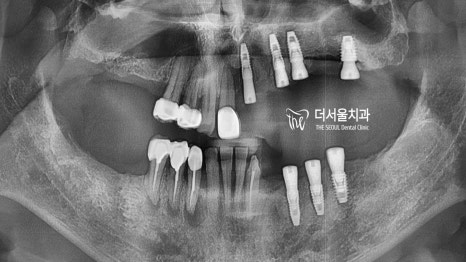

파노라마 상으로 살펴보니,

상하좌우.. 모두 성한 곳이 없었습니다.

남아있는 잔존치들의 상황도

그리 좋은 편이 아니였는데요.

특히 아래 신경치료를 받았던 곳들은

뿌리 끝 쪽에 큰 고름이 잡혀 있었습니다.

문제는 여기서 끝이 아니죠.

치조골 소실이 심하게 나타난 탓에

파란색까지 올라와 있어야 될 라인이

현재는 빨간색 밖에 되지 않는데요.

생각했던것보다 훨씬 심각한 상태였습니다.

아무래도 다량의 뼈이식,

다수의 식립을 동반하여

전체적인 문제를 개선해야겠네요.